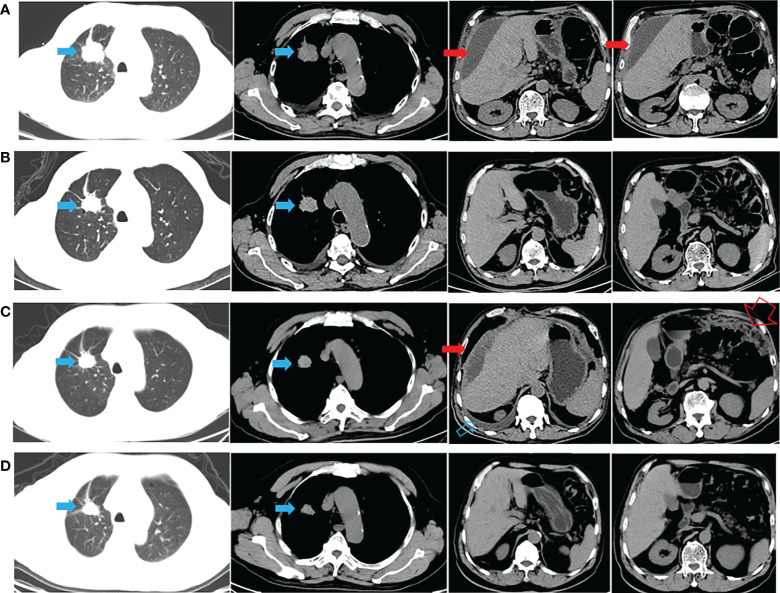

一名有大约 20 包年吸烟史的 72 岁男性主诉腹胀,于 2020 年 9 月 22 日入院。胸腹计算机断层扫描 (CT)(图 1A)和放射性核素骨扫描显示 2.8 厘米的右上肺肿块、胸水、腹水和多处骨转移(颅骨、右锁骨、多处椎骨和骨盆)。 彩色多普勒超声诊断左颈淋巴结转移。 CT引导活检示肿块为肺腺癌,诊断为右上肺腺癌多发转移(cT1bN3M1c,IVB期)。 2020 年 10 月 8 日,通过对一组 8 个癌症相关基因的下一代测序(NGS)分析了活检组织。在 EGFR 外显子 21(L858R)中检测到突变(丰度:14.5 %) 和 PIK3CA 外显子 8 (E474D)(丰度:36.6%),如图 2A 所示。 患者接受了第三代 TKI almonertinib(110 mg/d)和双膦酸盐(唑来膦酸,4 mg,q4w)的一线治疗。 贼初实现了疾病稳定,但患者贼终经历了疾病进展(出现胸水和腹水),无进展生存 (PFS) 时间为 12 个月(图 1B、C)。 疾病进展后,患者入住当地医院并接受顺铂(75 mg/m2,d1)和培美曲塞(500 mg/m2,d1)2个周期的化疗。 然而,胸水和腹水没有得到控制。 随后,患者入院,腹水沉渣诊断为转移性肺腺癌。 对腹水沉积物和 EGFR 外显子 21(L858R)(丰度:1.7%)、EGFR 外显子 18(L718Q)(丰度:0.8%)和 TP53 的突变进行重复检查 (V157F)(丰度:1.6%)被发现(图 2B)。

与多学科团队 (MDT) 讨论了患者的病例。 重要的是,患者已充分了解拟议治疗的益处和风险,并签署了知情同意书。 研究表明,与较高剂量的西妥昔单抗 (500 mg/m2) 相比,阿法替尼联合较低剂量的西妥昔单抗 (250 mg/m2) 可能具有更高的耐受性。 因此,2021年11月16日开始阿法替尼(40 mg/d)和西妥昔单抗(250 mg/m2,q2w)联合治疗。1个月后CT显示肺部和转移灶稳定,胸水和腹水控制良好( 图 1D)。 然后,每 2-3 个月进行一次随访,贼近一次随访时间为 2022 年 6 月 8 日。 轻微的胃肠道反应是观察到的少有不良事件 (AE)。 患者仍在接受联合方案治疗,生活质量满意,PFS近7个月。 从贼初的病理诊断开始,总生存期 (OS) 超过 21 个月(图 1 )。